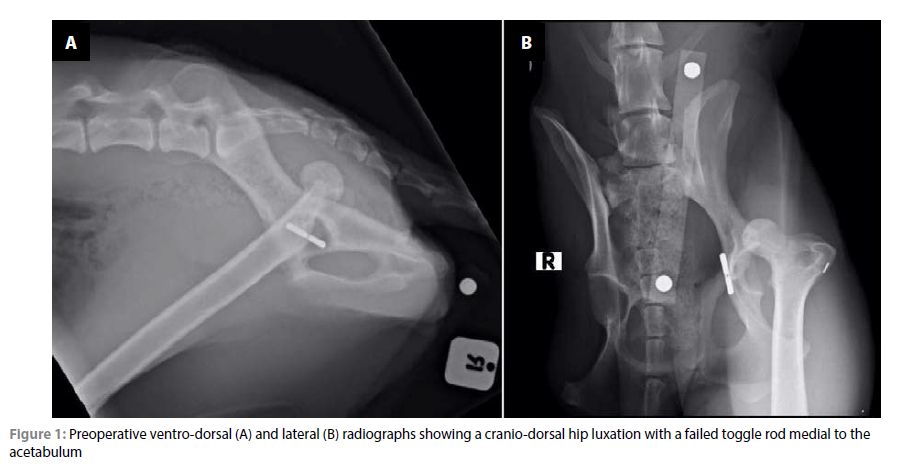

Postoperative radiographs were taken prior to the patient recovering from anaesthesia to assess implant placement and angulation of the implants relative to each other (Figure 2). The postoperative position of the radiographs showed an angle of lateral opening of the acetabular cup of 45°, 2-3° of inclination and 15° of retroversion. The femoral stem was positioned with 2-3° of anteversion and mild cranial caudal tilting in the femoral canal.